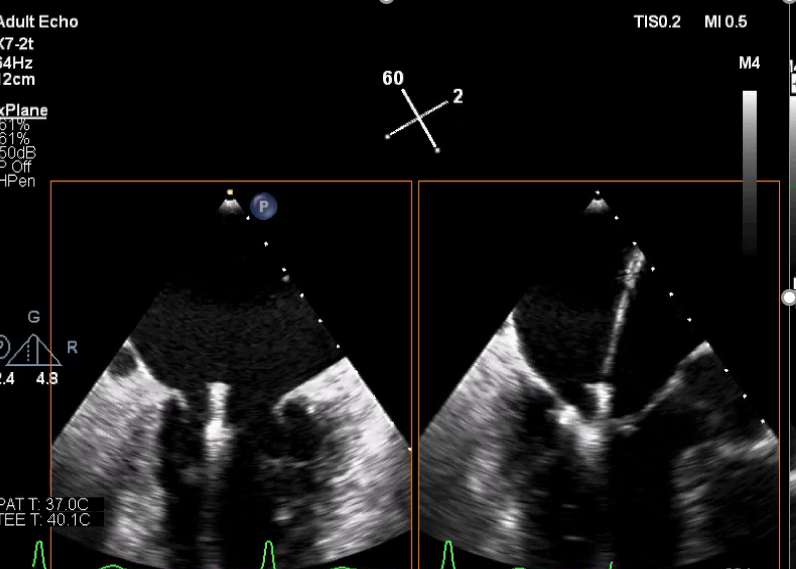

术中超声

确定房间隔穿刺点:靠后

2D视图下测量大鞘长度2cm

3D视图打开夹子

X-plane:下第夹子尝试捕获2区

X-plane:测量前叶长25mm,后叶长14.2mm

X-plane:计算前叶捕获长度8mm,后叶捕获长度7mm

3D视图下观察二尖瓣双孔形态

3D-color:残余少量返流